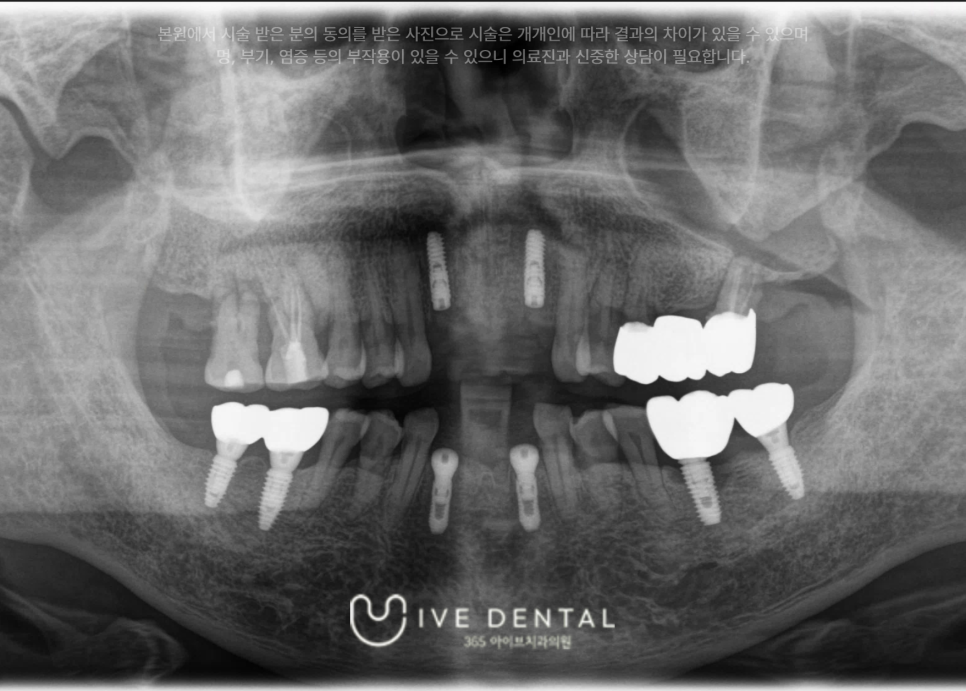

먼저 당일에 손상된 치아를 즉시 발치 후 상처 부위 봉합, 지혈과 함께 부러진 치조골을 고정하는 치조골 조정술을 시행하였습니다.

살릴 수 있는 가능성이 1%라도 있는 치아는 최대한 보존하고. 이미 파절 및 손상이 심하고 탈구가 되어

살릴 수 없는 치아에는 임플란트 식립을 같이 진행하였습니다.

당일에 처치 후 임플란트 fixture까지 식립한 후 사진입니다.

손상된 잇몸을 봉합하고, 지혈하고, 부러진 치아를 발치한 후 임플란트까지 식립하면 일단 일차적 처치는 끝나게 됩니다.